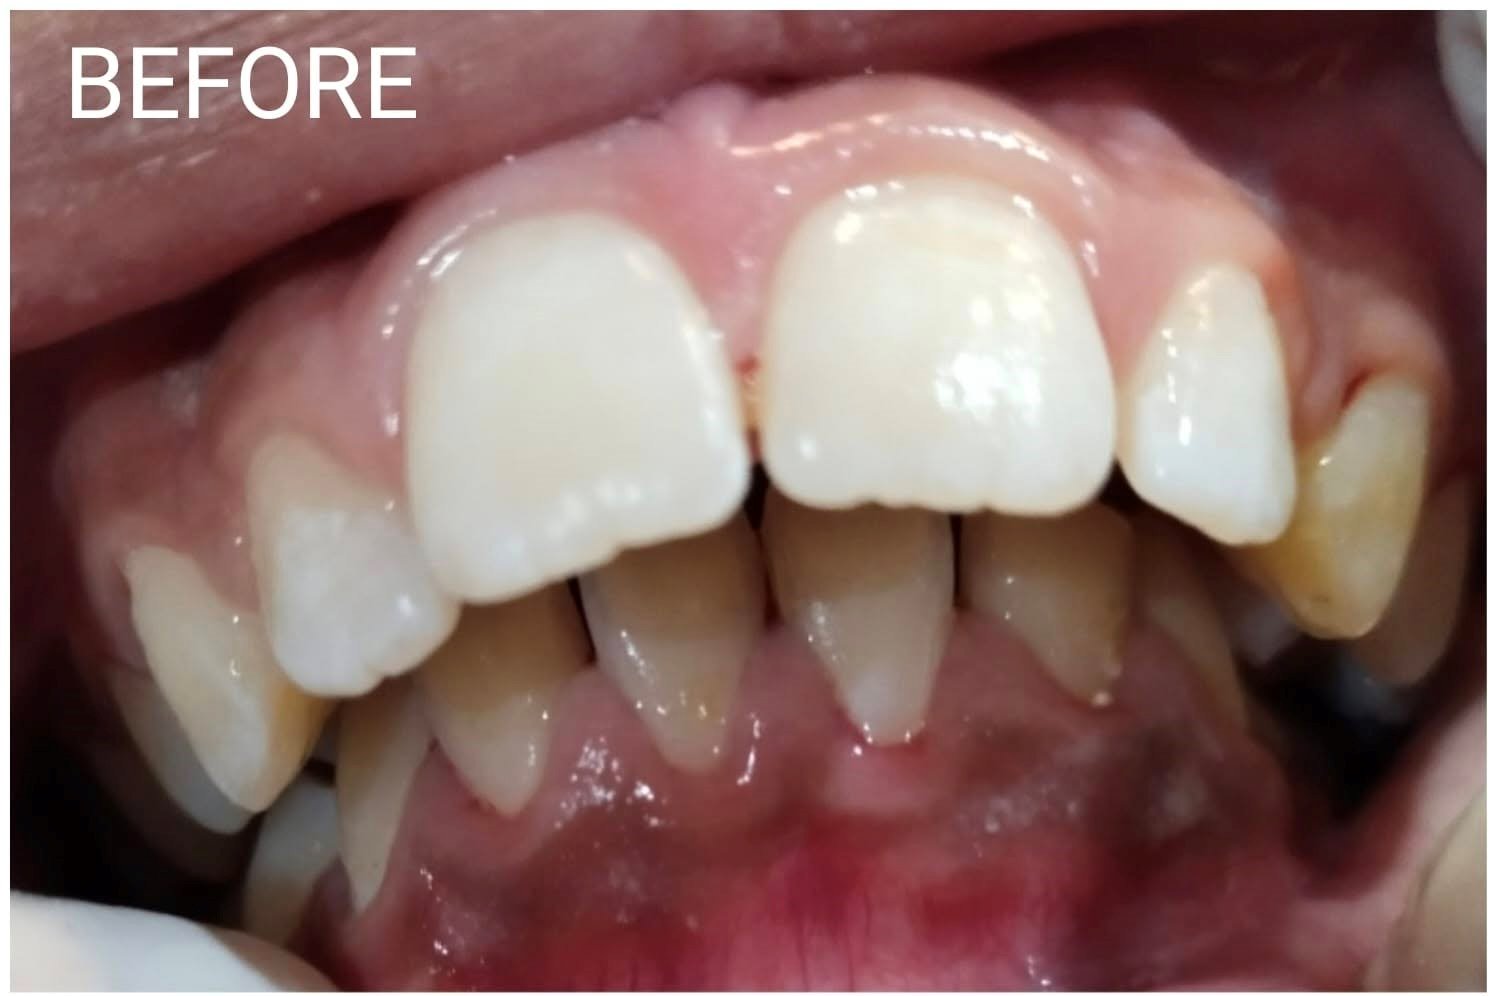

"I had a cavity in my tooth 2 years ago and gradually that tooth decayed and I was very worried. I couldn't even eat anything. Then I consulted Dr. Atif and got a root canal done by him. Now, thank God, I have gotten a lot of relief. Now I can eat comfortably. Now I don't even feel hot or cold in my teeth. Thank you (Dr. Atif Malik) "